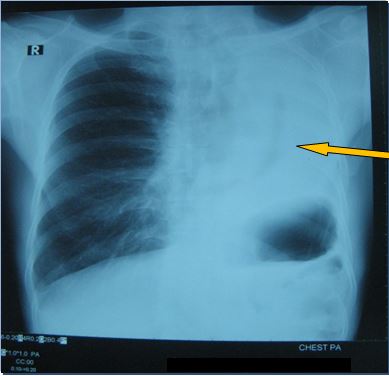

+ Chụp X- Quang ngực đánh giá lại sau 5 tháng điều trị: Khối u thùy trên phổi trái biến mất

Sau điều trị 5 tháng

Không rõ đám mờ